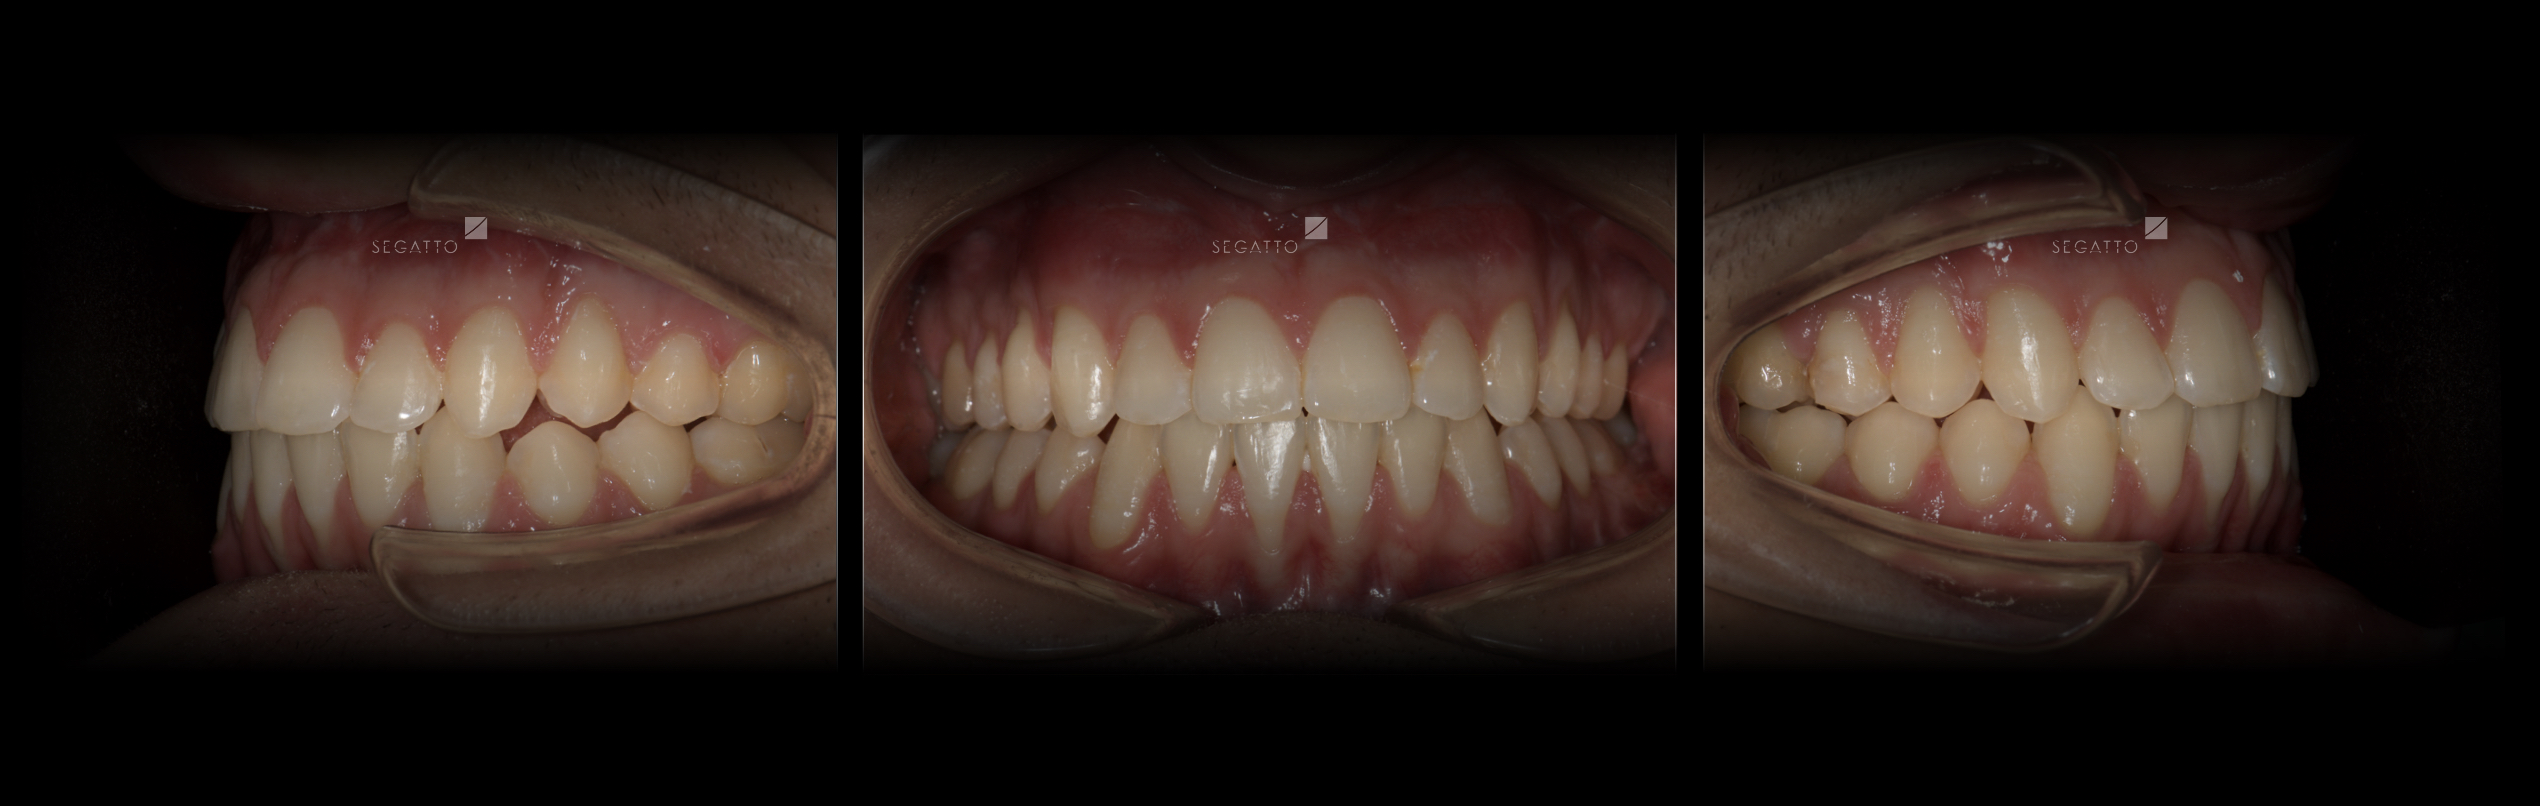

Orthodontics

Cases